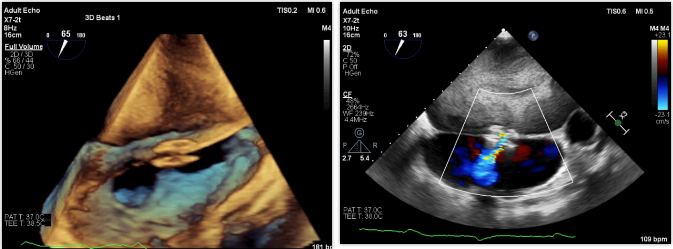

手术在全麻下进行,右心导管检查肺动脉压25/13(17)mmHg,肺小动脉楔入压22/11(15)mmHg(使用Fogarty取栓导管测量),右心房压12/6(8)mmHg,全肺阻力411dyn·s·cm-5,肺血管阻力48dyn·s·cm-5,心输出量3.3L/min,心指数2.5L/min,Qp/Qs=1。X线加食道超声引导下经皮房间隔穿刺成功后送入预塑形左房导丝(武汉唯柯医疗 伦理批件:武汉协和2020-0165号)建立轨道,选择8mm外周动脉高压球囊(波士顿科学)对房间隔进行扩张,送入9F专用输送系统(武汉唯柯医疗 伦理批件:武汉协和2020-0165号),体外充分排气后送入20-6mm心房分流器至房间隔处支撑此前球囊撕开的不规则房间隔造口,透视及超声下观察分流器形态位置良好,分流器孔径约6mm,左向右分流流速0.8m/s,三尖瓣反流减轻至中度。术后右心导管测量肺动脉压27/11(16)mmHg,左心房压15/6(9)mmHg,右心房压13/4(7)mmHg,全肺阻力234dyn·s·cm-5,肺血管阻力105dyn·s·cm-5,Qp/Qs 1.38,心输出量4.1L/min,心指数3.1L/min,顺利完成手术。

术后患者即饮食恢复,未再呕吐,活动后胸闷气喘症状几乎消失,术后一般体力活动基本不受限制。纽约心功能分级II级,三个月随访显示六分钟步行距离406米,较术前↑。堪萨斯心肌病问卷得分77.27分↑。心肺运动试验:峰值摄氧量/体重14.6ml/min/kg↑,百分预计值63%↑,无氧阈 12.5ml/min/kg↑。心脏超声检查:分流孔直径约6mm,左向右分流流速1.4m/s,左心房容积1050mL↓,三尖瓣轻-中度反流↓,流速2.7m/s。右心导管检查:测量肺动脉压28/13(27)mmHg,左心房压14/6(9)mmHg,右心房压12/3(6)mmHg,全肺阻力273dyn·s·cm-5,肺血管阻力196dyn·s·cm-5,Qp/Qs 1.32,心输出量4.3L/min,心指数3.2L/min。